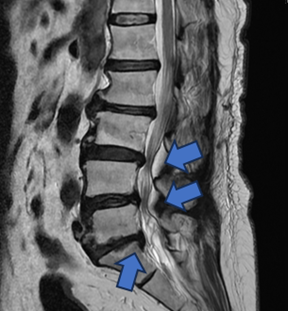

【記者張原銘、張皓傑台中報導】65歲婦人,長期飽受腰痛、下肢痠麻及坐骨神經痛所苦,行走距離逐年縮短,嚴重影響日常生活。過去曾接受膝關節保膝手術及脊椎內視鏡減壓治療,初期恢復良好,惟因仍存在多節段腰椎退化性狹窄與骨刺問題,加上彎腰負重及久坐等生活習慣未能完全改善,症狀逐漸惡化,甚至出現神經性跛行。經臺中市立老人復健綜合醫院骨科部副部長林琮凱醫師詳細檢查後,診斷為第三、四、五腰椎合併第一薦椎之多節段脊椎狹窄與神經壓迫。醫療團隊與病患及家屬充分溝通後,決定採用電腦導航輔助之前位/前側位脊椎融合手術,並合併後方骨釘固定,一次完成多節段重建。術後病患神經症狀明顯改善,行走能力恢復,生活品質大幅提升。

林琮凱醫師指出,中高齡族群若長期出現腰痛、臀部或下肢痠麻刺痛,甚至走一小段路就必須停下休息,往往與退化性腰椎狹窄及神經受壓有關,並非單純老化現象。研究顯示,60歲以上族群約有20至30%可在影像檢查中發現腰椎狹窄,若未及時處理,恐導致下肢無力、行走困難,嚴重者甚至影響排尿、排便功能。醫師建議,平時應注意姿勢調整、避免彎腰負重、加強核心肌群訓練;此類患者也不適合久坐小板凳或躺沙發,否則容易加重症狀。當保守治療效果有限時,及早接受專業評估並選擇合適的微創手術,有助於有效解除神經壓迫。